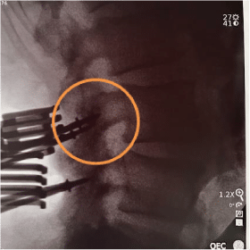

In this approach Caspar pins are placed at the selected entry point for each screw. Once in place a single lateral X-ray and A/P X-ray acquired.

Dr. Thompkins utilizes the pins as reference points to assess each screw’s entry point, angulation, and congruency which allows him to plan any trajectory modifications with the Bolt Navigation System. As an example on the right, Dr. Thompkins corrected the angle of the top right pin while planning and, per the above post-placement X-ray, achieved optimal screw placement.

The use of CBT trajectory requires increased accuracy due to the narrow anatomical placement corridor. In this case, the Bolt Navigation System allowed precise placement of cortical screws with a more confined midline surgical access with a straight-on, slightly cranial and divergent screw angulation away from neural elements. Further, it provided fixation through the medial and lateral portions of the cortex providing advanced bony purchase.

The Bolt Navigation System offers Dr. Thompkins the ability to quickly and easily achieve the benefits of cortical trajectory with minimal radiation exposure.2,3 The System leverages limited intraoperative X-rays and the patient’s existing pre-operative MRI or CT to provide efficient, precise, and low-radiation navigation for this minimally invasive approach.